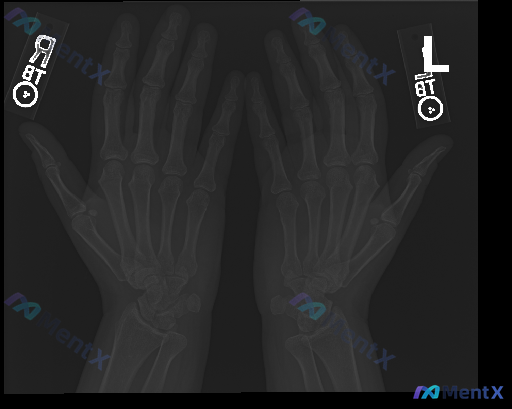

整理到一组影像与临床结合的资料,想和大家讨论下这种情况的思路: 基本情况: - 影像学检查:双侧手部正位X光 - 影像所见:骨骼结构完整,骨皮质连续,未见明确骨折线、脱位;各关节间隙尚可,未见明显狭窄或破坏;骨密度、骨端形态大致正常;软组织影未见明确肿胀、钙化或占位。 - 影像初步总结:双侧手部正位...